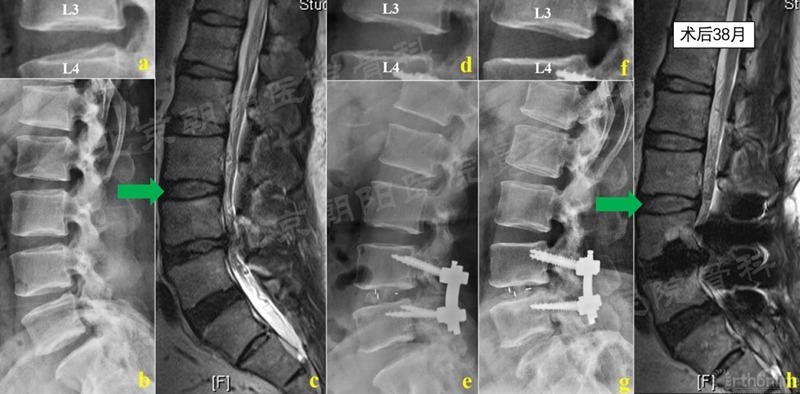

典型病例1.CBT-PLIF术后患者38月随访复查MRI,邻近节段椎间盘未见明显退变,Pfirrmann分级1->1级,椎间隙高度维持良好。